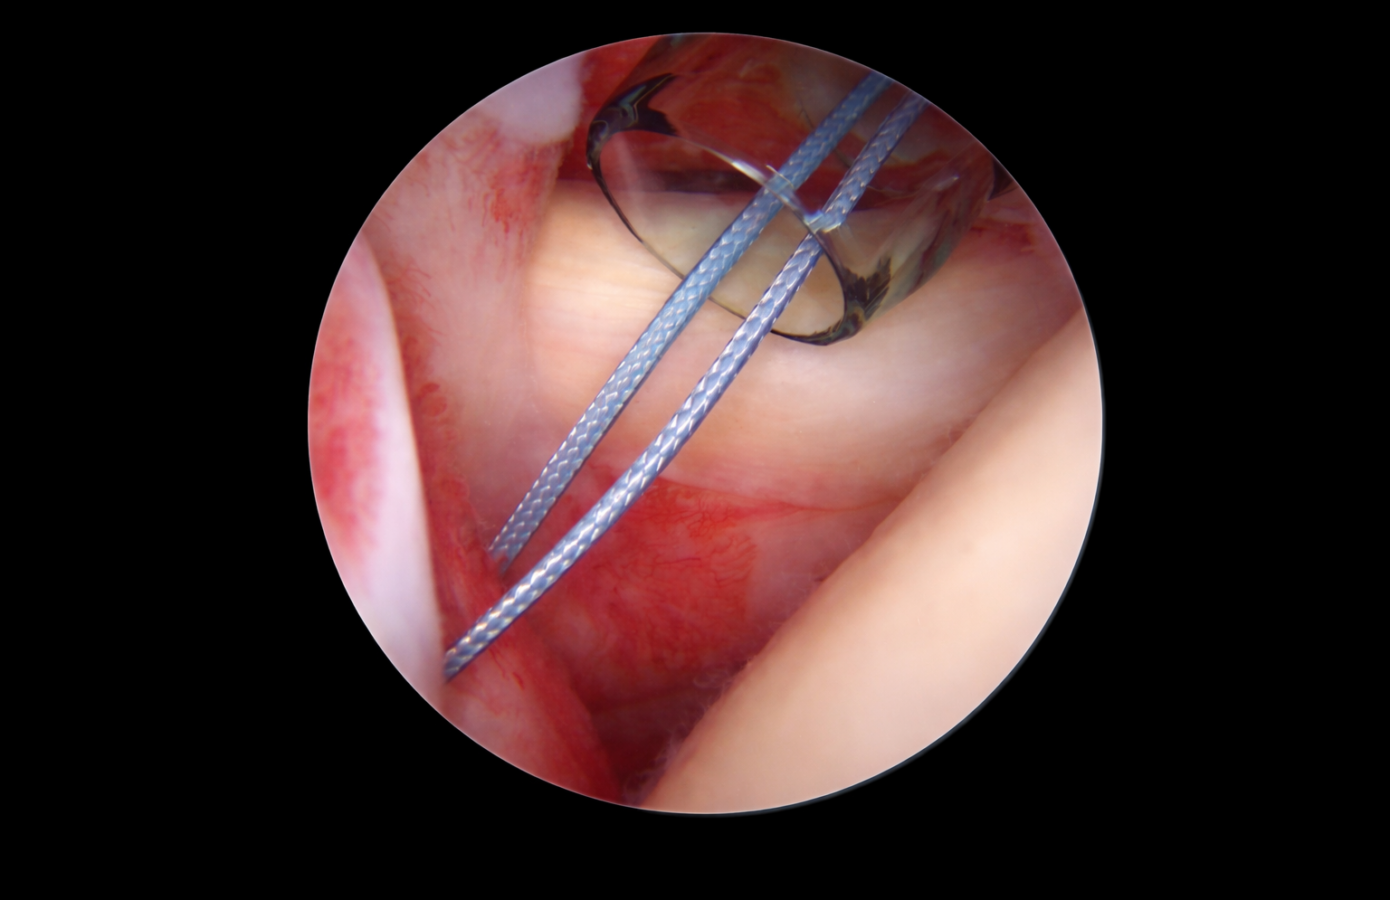

Coatings and surface engineering

Surface modifications engineered to enhance functionality while maintaining textile integrity and scalable manufacturability.

• Silicone for lubricity

• Wax for handling optimization

• Dyes for visibility

• Collagen for tissue interaction